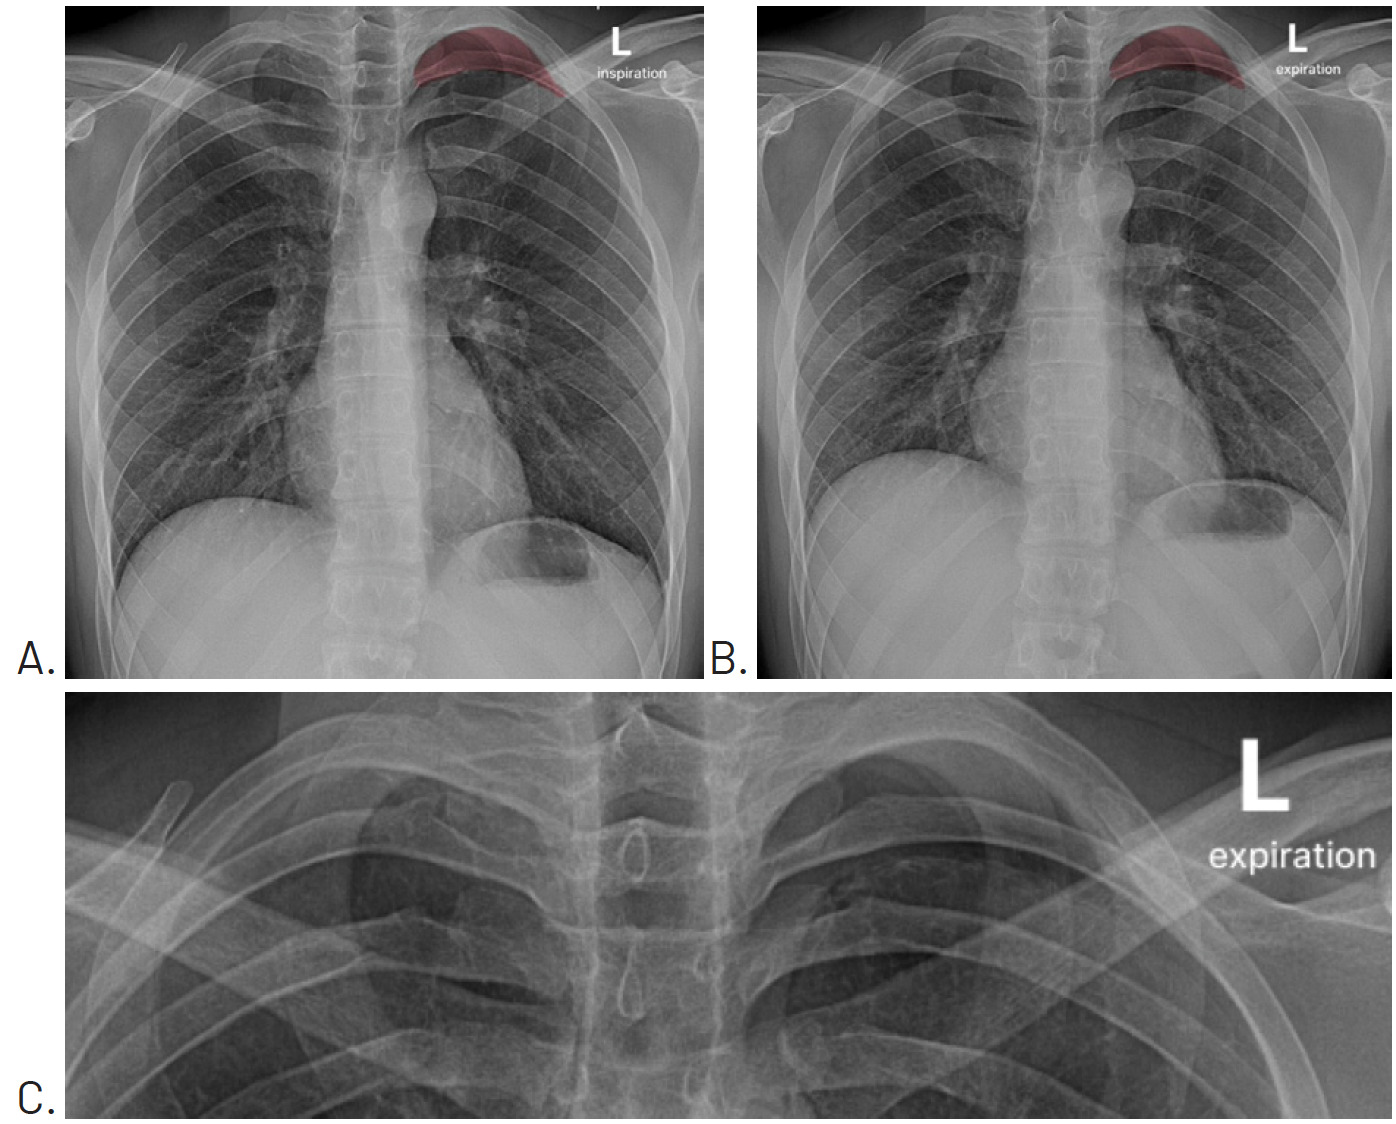

A posterior to anterior chest, posterior to anterior left rib, and left oblique rib were performed the day after examination. No fracture was evident. However, the chest image included what appeared to be a small pneumothorax at the apex of the left lung field. The attending radiologist asked that the chest x-ray be repeated with both inspiration (Figure 1A) and expiration (Figure 1B). These views confirmed the presence of a small pneumothorax at the apex of the left lung.

Since the patient was not currently experiencing respiratory distress, he was told to monitor his symptoms over the weekend, and that should any worsening occur in his pain or ability to breathe to seek emergency medical care. Four days later, a repeat chest x-ray with inspiration (Figure 2A) and expiration (Figure 2B) views was performed and showed that the pneumothorax had resolved.